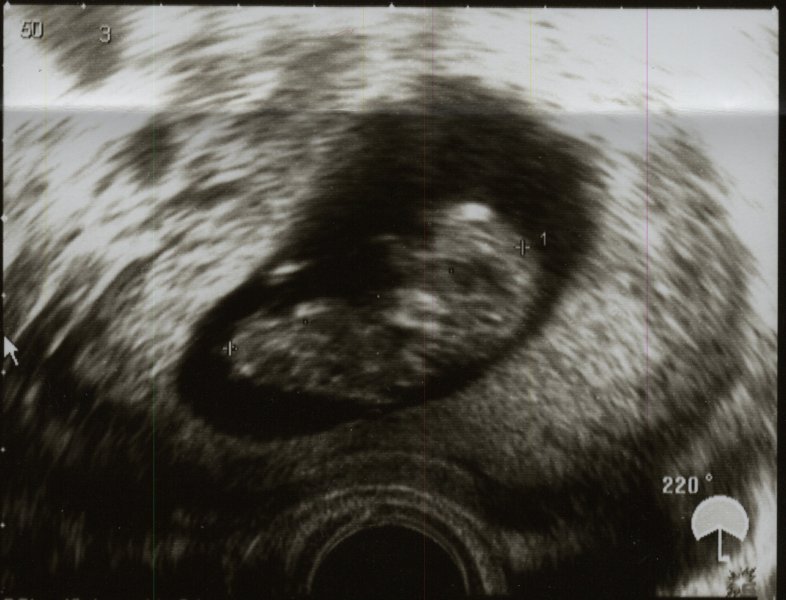

Bleibt nur noch eine Frage: wer ist wohl das Baby auf dem letzten Bild? ;-)